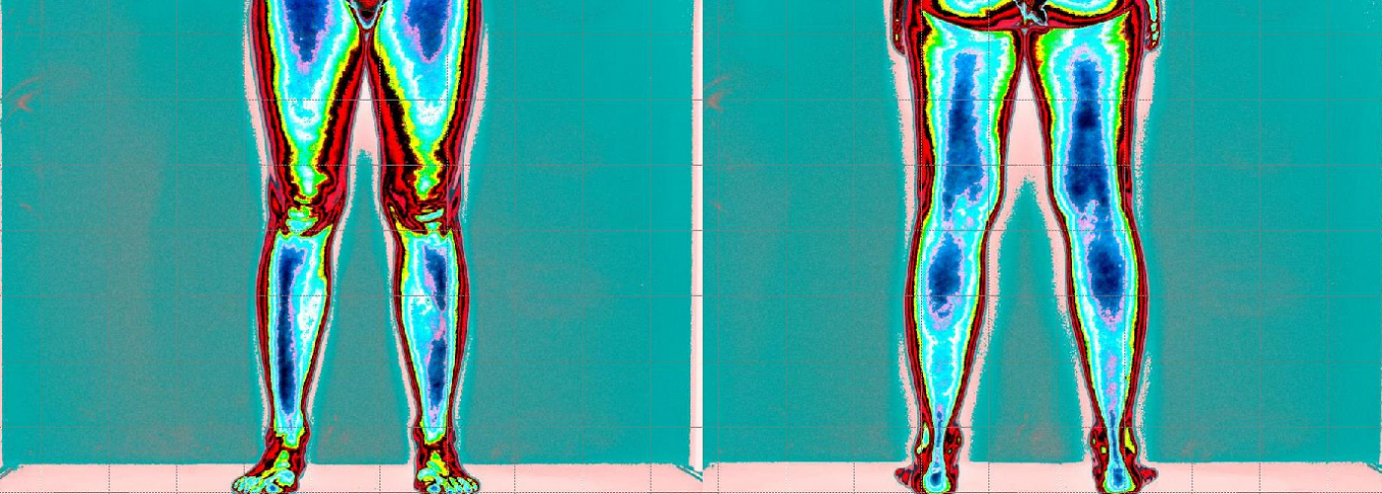

Prima, minima tensione muscolatura posteriore del tronco è arti inferiori.

Forte tensione muscolatura glutei a compensare.

Dopo il trattamento con Renovatio possiamo notare una normalizzazione della tensione muscolare posturale.

Con conseguente scomparsa delle problematiche di dolore Lombo-sciatalgia

Prima, minima tensione muscolatura posteriore del tronco è arti inferiori.

Forte tensione muscolatura glutei a compensare.

Dopo il trattamento con Renovatio possiamo notare una normalizzazione della tensione muscolare posturale.

Con conseguente scomparsa delle problematiche di dolore Lombo-sciatalgia